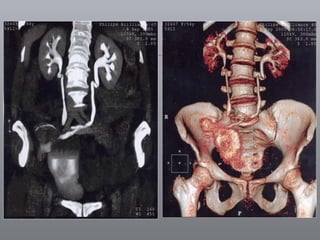

Câncer de Bexiga Estudos de imagens Diagnóstico Ultrassonografia Urografia excretora Estadiamento CT RNM Rx tórax  Cistoscopia + biópsia + biópsias randomizadas

CT